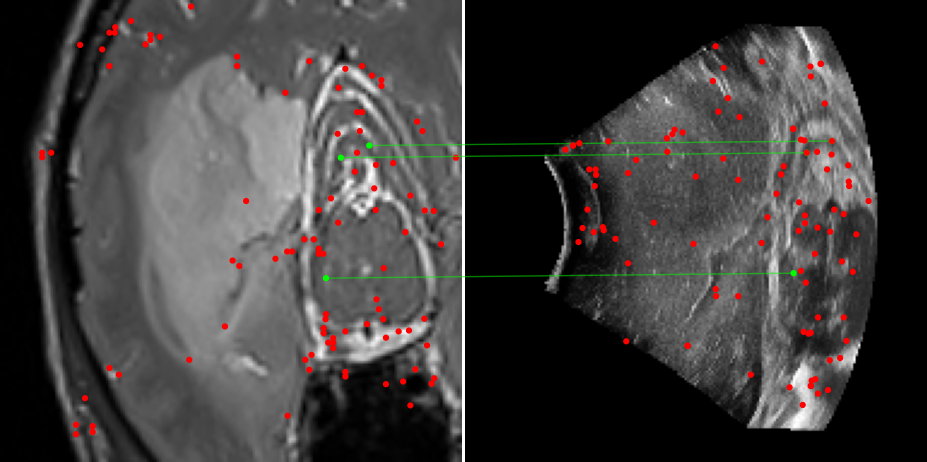

Figure 3: Examples of matching on three cases, one per column (MR on left and US on right). From top to bottom: SIFT+Cosine, MIND+Cosine, SP+Cosine, SP+LG, Ours+LG, Ours+Cosine. Correct matches recovered by each method are shown in green lines and mismatched are shown with a red dot.